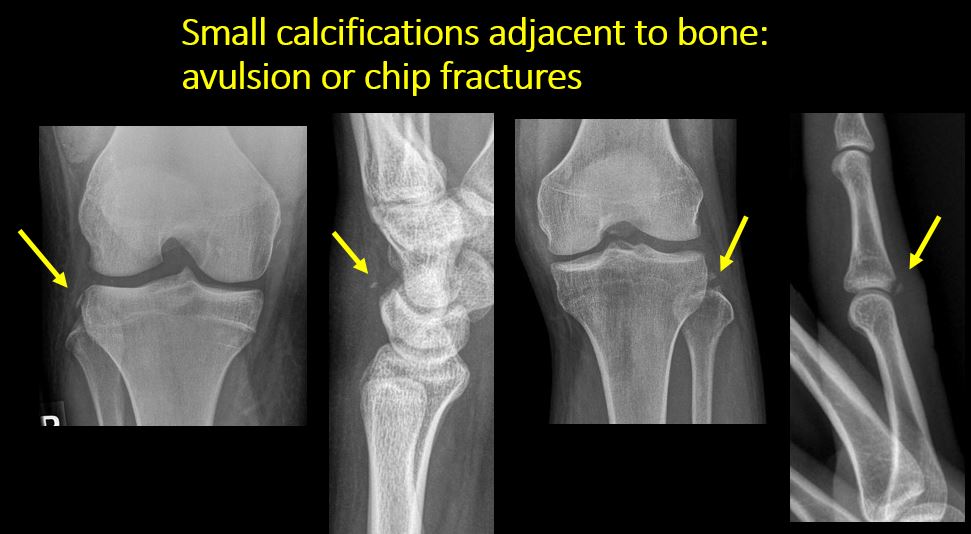

There is a displaced fragment which may be from avulsion by a tendon, or joint capsule or from a comminuted or other fracture.